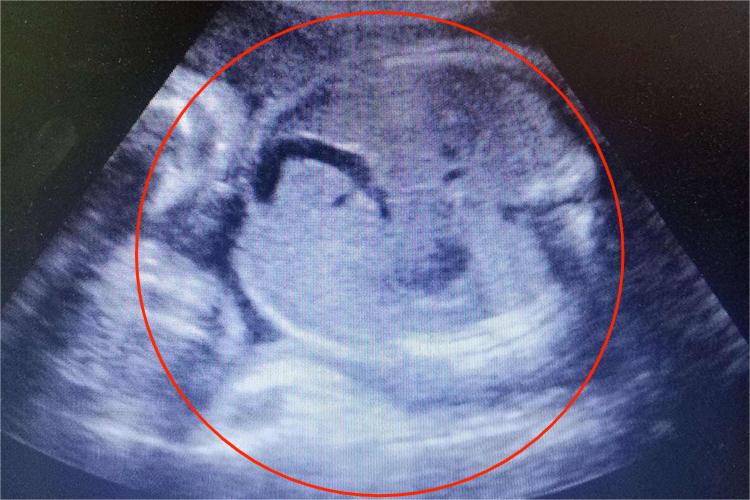

怀孕八个月属于晚期妊娠,此时进行彩超检查会发现胎儿各器官已发育齐全。可以通过彩超判断胎方位、胎先露,以及评估胎儿体重等。

怀孕八个月时各器官已经发育齐全,胎儿身长约40cm,顶臀长28cm,体重约1700g。此时胎儿的皮肤为深红色,且仍呈皱缩状。